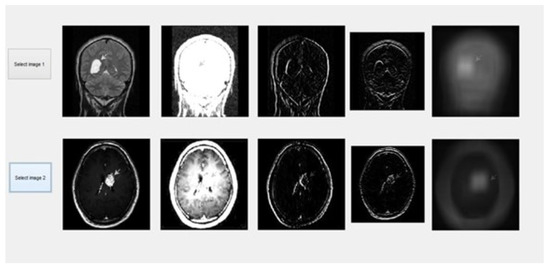

After introducing hybrid algorithms “(DCT, SWT, IHS, PCA, average)”, the next step was to implement them. To do this, we employ the “C programming” language. This code was included using MATLAB. The rule-based inclination combination in the “Dual-Tree Complex Wavelet” region was accomplished using various images from a standard image database and constant images as shown in Figures as shown in Figure 7, Figure 8 and Figure 9. The effectiveness of the suggested combination approach is demonstrated strongly with specific images, such as “multi-sensor images”, “multispectral remote detection” images, clinical images, “CT”, “MR images”, and “surreal images” [47]. We may also blend ongoing images.

Figure 9. Spatial gradients computed by smoothing the average input images.

Information 15 00612 g009